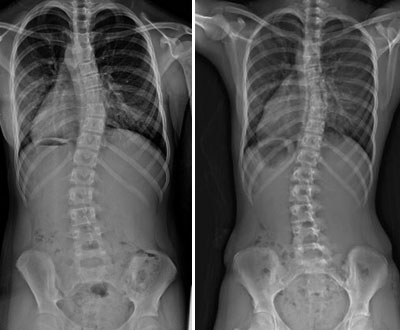

1.04.2017 avaneb Eesti inimestel, kel probleeme seljaga või tegelevad teiste ravimise või nõustamisega, kohtuda ja osaleda seminaril, mille viib läbi Tallinnas Moskva Ülikooli professor Jerjomuškin. Eelkõige peatub professor skolioosil, selle vältimisel ja ravi võimalustel. оукощьгылшт Professori seminar aprillis Tallinnas toimub 1-päevane seminar teemal „Seljaprobleemid, nende vältimise- ja ravi võimalused“. Seminaril on tähelepanu keskpunktis skolioos. Hommikupoolsel osal toimub teoreetiline loeng, kus selgitatakse selja probleemide eelkõige skolioosi tekkepõhjuseid, olemust, vältimise- ja ravivõimalusi. skolioos_selg Päeva teise poole täidab praktiline õpituba, kus külalislektor-arst-ortopeed tutvustab praktilisi võtteid ja harjutusi, et vältida skolioosi teket või leevendada juba olemasolevat kõrvale kallet või stabiliseerida inimese seisundit. Õpitoas võimalus saada vastused selja probleemidega seotud küsimustele! Jerjomuskin on suurte kogemustega arst-ortopeed-õppejõud Moskva Ülikoolis, mitme ravimassaaži õpiku autor ja Veneföderatsiooni massööride juhtkonna liige.   Kuna seminar on ka praktiline, on kohtade arv piiratud. Kõik seminaril osalejad saavad EMTK tunnistuse osalemise kohta. Seminari hind 125 EUR, registreerides enne 01.03.2017 hind 110 EUR EML liikmetele hind 99 EUR   *Kursuse täpne kellaaeg on täpsustamisel. Lisainfo ja registreerimine aadressil koolitused@massaaz.ee